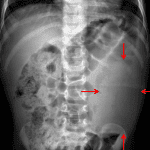

- Large soft tissue density in the left hemiabdomen with rightward displacement of multiple bowel loops

- Abdominal mass (Wilms tumor)

Large soft tissue density in the left hemiabdomen with rightward displacement of multiple bowel loops. Recommend ultrasound for further evaluation.

Nonobstructive bowel gas pattern with a moderate volume of stool in the ascending colon.